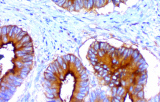

L’immunoistochimica (IHC) con anticorpi primari CE/IVD è essenziale per una diagnosi e classificazione accurata sia delle malignità ginecologiche che mammarie. Questi anticorpi consentono la rilevazione precisa di marcatori tumorali e proteine cellulari, supportando la diagnosi differenziale e guidando strategie terapeutiche personalizzate.

Studi recenti sottolineano il valore diagnostico delle proteine del complesso SWI/SNF, in particolare ARID1B, nell’identificazione di malignità ginecologiche dedifferenziate e indifferenziate – tumori aggressivi con prognosi sfavorevole. L’IHC di ARID1B offre alta specificità e viene sempre più integrata nei pannelli diagnostici per migliorare la precisione. Pannelli con marcatori aggiuntivi supportano anche la differenziazione dei sarcomi uterini, aumentando l’accuratezza diagnostica. Evidenze emergenti suggeriscono che ARID1B potrebbe rappresentare un potenziale bersaglio terapeutico nel carcinoma ovarico a cellule chiare, sebbene le applicazioni cliniche rimangano in fase di ricerca.